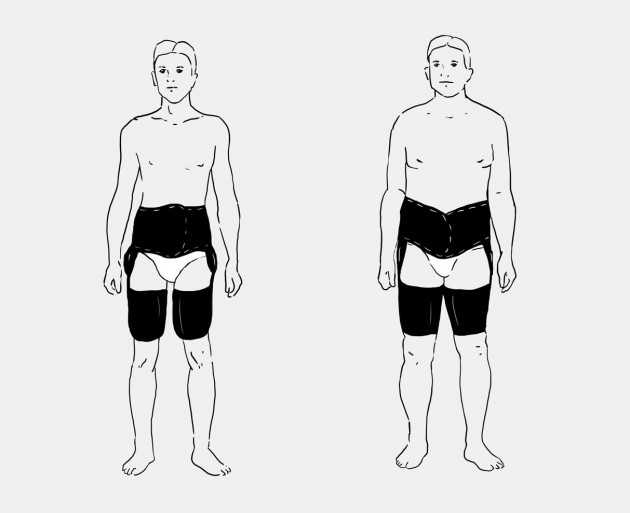

Tabela rozmiarów

| Rozmiar | Obwód w pasie | Sposób dokonywania pomiaru |

|---|---|---|

| Uniwersalny | min 75 – max 125 cm |  |

Maksymalna waga użytkownika do 75kg.

Całkowita długość ortezy:

min: 53 cm

max: 67 cm

Orteza VIPERdual to orteza stabilizująca stawy biodrowe, pozwalająca na regulację ich ruchomości w zakresie co 15 stopni bądź na całkowite ich unieruchomienie. Orteza została wykonana z surowca ActiveDistance oraz ActiveDistance II i wyposażona w uniwersalny kosz biodrowy, dwie opaski udowe oraz dwie jednoosiowe szyny boczne z regulacją ich długości oraz kąta zgięcia i wyprostu co 15 stopni.

Kosz biodrowy posiada anatomiczną konstrukcję pozwalającą na płynną regulację jego obwodu. Regulacja ta jest możliwa dzięki funkcji samoszczepnej surowca, z którego wykonano wyrób, oraz dzięki tylnemu zapięciu. Obwód kosza dopasowuje się do danego pacjenta, poprzez odcięcie zbędnej części ortezy, wzdłuż specjalnie przygotowanych kanałów. Przednie zapięcie kosza biodrowego, zostało tak zaprojektowane, aby pasowało do każdego typu sylwetki.

Dodatkowo, kosz biodrowy wyposażono w dwie plastikowe peloty boczne, w które zamontowano szyny ortopedyczne oraz dwa komplety mocnych pasów obwodowych z możliwością płynnej regulacji ich długości.

W wyrobie zastosowano również dwie opaski udowe, z których każdą wyposażono w pelotę plastikową i dwa pasy obwodowe o regulowanej długości.

Nasza orteza VIPERdual jest wyrobem bardzo lekkim o ażurowej konstrukcji, co zdecydowanie ułatwia użytkowanie jej po operacji biodra. Wyposażono ją w dwie monocentryczne szyny boczne z regulacją kąta zgięcia i wyprostu. Szyny wykonano z wysokiej jakości stopu aluminium i pokryto na gorąco trwałą powłoką proszkową. Układ szyn w ortezie i ich kształt gwarantują anatomiczne przyleganie wyrobu do biodra i kończyny oraz pozwalają na uzyskanie doskonałej stabilizacji zabezpieczonego stawu.